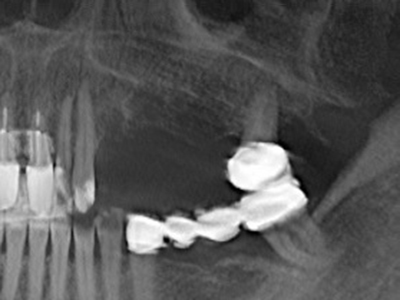

Bei der Knochenblockentnahme zeigen sich weitere Vorteile für die Piezochirurgie: Neben der bereits beschriebenen hohen Präzision bei der Osteotomie stellt sich gerade die Verwendung der dünnen Sägespitzen als besonders materialschonend heraus. Bei der Verwendung insbesondere von Lindemannfräsen sind mit deutlich höheren Entnahmeverlusten durch die dickere Instrumentenspitze zu rechnen (Lakshmiganthan, Gokulanathan et al. 2012). Die insbesondere bei retromolar entnommenen Blocktransplantaten notwendige basale Abtrennung wird durch speziell hierfür vorgesehene rechtwinklige Sägen erleichtert, so dass die Piezochirurgie als präzises, übersichtliches und sicheres Verfahren zur retromolaren Knochenblockgewinnung angesehen wird (Happe 2007) (Abb. 1-12).